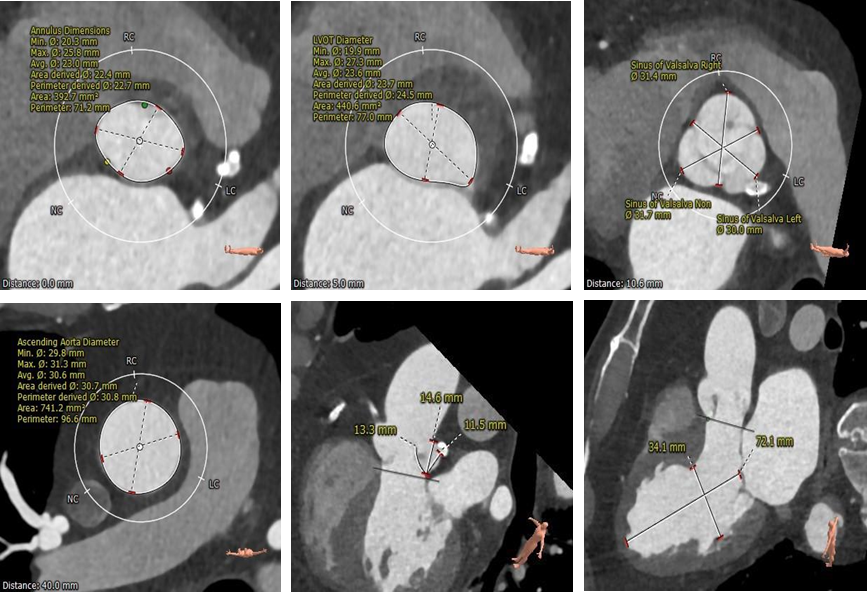

CT显示Type0型二叶瓣,瓣叶中重度钙化伴增厚粘连,存在人工瓣膜形变、瓣环撕裂及根部损伤风险;大瓣环、钙化分布不均匀及瓣口形态限制,人工瓣膜锚定难度较高,瓣周漏风险高,存在瓣中瓣风险。严重横位心(75°),输送系统过弓、跨瓣难度较高。

首先,瓣膜尺寸选择。瓣膜尺寸的选择是TAVR手术成功的关键因素。例如大部分二叶瓣狭窄表现为瓣叶+瓣环的“火山口”立体结构,因此需要综合考虑主动脉瓣瓣环和瓣环上结构进行TAVR瓣膜尺寸的选择。不论是基于环上结构进行瓣膜选择的策略,还是基于球囊扩张制定瓣膜尺寸,均倾向于Downsize策略,选择更小型号的瓣膜进行植入。鉴于反流患者增加瓣膜锚定的难度,反流患者的瓣膜选择也需要慎重,需要术前根据整个锚定区解剖来评估瓣膜尺寸的选择,避免瓣膜移位影响其他解剖结构。

其次,术中投照角度选择。合适的投照度能够帮助临床将3维结构2维化,获得更好的观察角度。二叶瓣患者TAVR术中需要选择双窦展开的体位,这个角度下边能够更好的在DSA上看到两个窦的展开情况以及瓣膜的贴合情况。对于反流的患者,我们更加关注植入过程深度的变化,故采用Cusp Overlapping技术。手术过程中为保障瓣膜精准的定位,术中我们会先释放到输送器胶囊与瓣架底端齐平的位置再造影判断其与窦底位置,进而慢慢释放让瓣膜与组织贴靠,提供锚定力后再快速释放到工作位,进而多体位造影+超声评估,如果不合适再回收进一步调整。